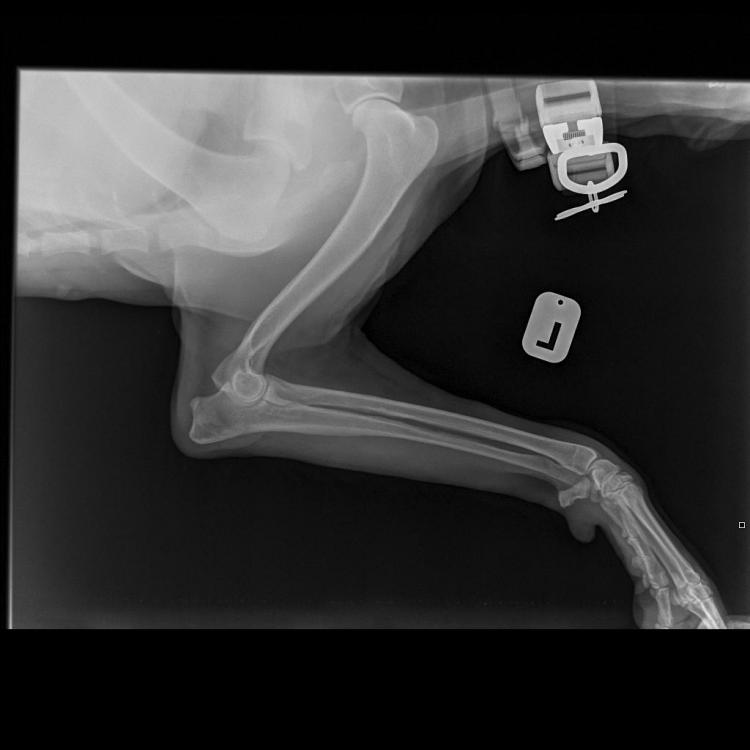

Яся&Лина&Лора Опубликовано 4 июня, 2020 Опубликовано 4 июня, 2020 Теперь все по порядку. Друзья, спасибо за терпение и выдержку! Писала на бегу. И, конечно же, спасибо за поддержку! В общем, Никуня нас немножко сегодня испугала, если честно. Поэтому побежали не раздумывая, выяснять что случилось с лапой. Как понимаете, боишься уже всего! В клинике нас встретил давно знакомый и совсем не страшный доктор Климухин И.Н. Очень внимательно и долго нас осматривал и щупал. Потом уже в конце приема сказал, что Никуся невероятно терпеливая девочка, молчит и терпит до последнего, даже никаких звуков не издаёт. Потом мы сделали 3 рентгеновских снимка и сдали кровь: общий и б/х (для контроля перед назначением обезболивающих). Кровь сдавали и температуру мерили с настоящим голдячим достоинством! Ну, правда... немножко случилась экспресс-линька.... Мне кажется, в Нике осталась вся клиника! Доктор нам отзвонился по анализам очень быстро. Анализы у нас прекрасные! Ура! За исключением повышенных лейкоцитов. Поэтому нужен контроль на фоне лечения через несколько дней. По рентгену криминала тоже нет никакого. По результату осмотра, есть небольшие проблемки с суставами, но ничего критичного. При этом, однозначно есть хромота на правую лапку, а реагирует при осмотре и левая тоже. Предположили, что, возможно, Никуся неудачно кувырнулась дома или оступилась?! Последнее время дожди и мы никуда не выезжали. Дома Никуся на диван залазит крайне редко. Внизу травмироваться вроде как негде?! Гуляет она всегда с огромным удовольствием. Возможно, на улице неудачно рванула вперед. Но, слава Богу! Ничего не порвала! И не вывихнула! В итоге доктор нам назначил Превикокс на 5 дней. В воскресенье ждет нас на контрольный осмотр, чтоб оценить динамику и надо будет повторить общий анализ крови, посмотреть лейкоциты. Счастью не было предела, волшебное слово «домой»! За все страдания получила немного вкуснях. «Где тут вкусняхи дают?» «Ням ням» «А мы уже домой?! Правда?!» «Тогда можно и расслабится!» «Поехали уже! Че стоим?!» 7